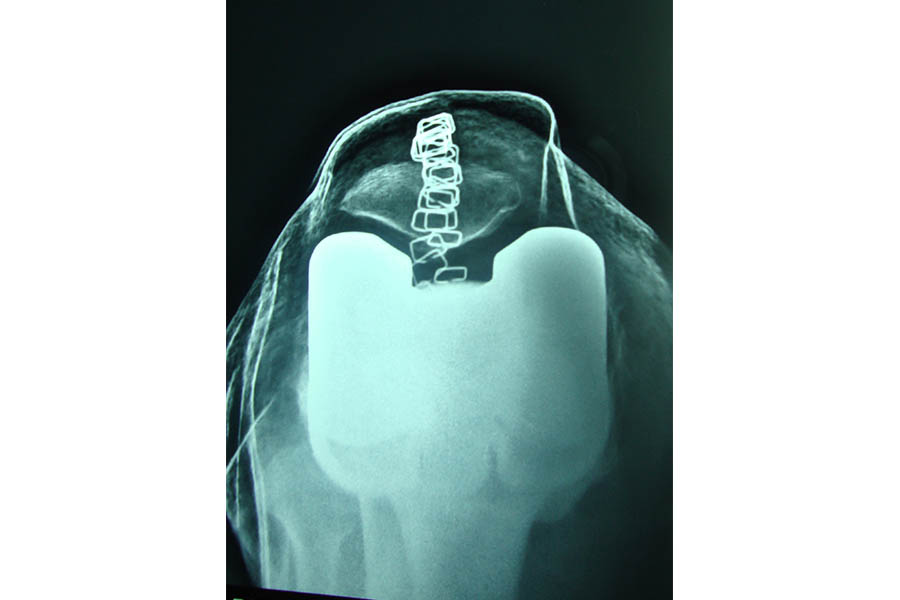

Total Knee Replacement

Case 1